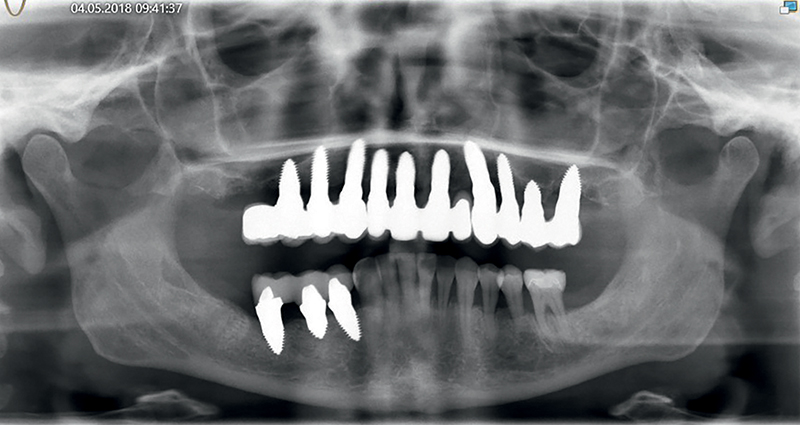

Caso 4: Una paziente, fumatrice, con parodontite avanzata e numerose cisti periapicali in entrambe le regioni superiori posteriori, presentava perimplantite terminale a carico degli impianti in titanio pre-esistenti, grave mobilità dei denti e marcata perdita ossea in tutte le regioni del mascellare. Inoltre, si osservava uno spostamento della linea mediana di ca. 4 mm, con denti mancanti (12 e 22). La maggior parte dell'osso alveolare buccale dei denti 11 e 21 era già andata perduta, e la linea del sorriso alta del paziente presentava sfide estetiche. Per compensare lo spostamento della linea mediana e creare una dentatura regolare da 16-26, la paziente optava per il posizionamento immediato di impianti a carico immediato (attraverso riabilitazione con protesi provvisoria a lungo termine), per un totale di 10 fixtures nell'arcata superiore. Gli impianti venivano attentamente monitorati, così come le condizioni parodontali della paziente. Dopo 6 mesi gli impianti venivano finalmente preparati e dotati di corone in ceramica definitive. Nello stesso periodo la paziente acconsentiva anche all’inserimento di un impianto nella regione dei molari inferiori, che portava ad una completa riabilitazione orale. Subito dopo il primo intervento chirurgico (rimozione di tutti i denti infiammati e degli impianti in titanio nel mascellare superiore, ed inserimento immediato di 10 impianti in ceramica a carico immediato), lo stato di salute generale del paziente migliorava notevolmente, come chiaramente veniva confermato 7 anni dopo (Fig. 18-21).

Fig. 19 (caso 4) - Radiografia e CBCT che mostrano difetto e perdita di struttura ossea

Fig. 20 (caso 4) - Immagine di controllo radiografica a 12 mesi dall'inserimento degli impianti